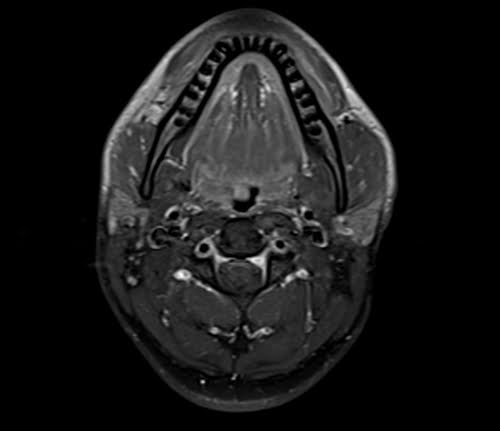

MRI Soft tissue neck axial T1 fat sat post contrast images